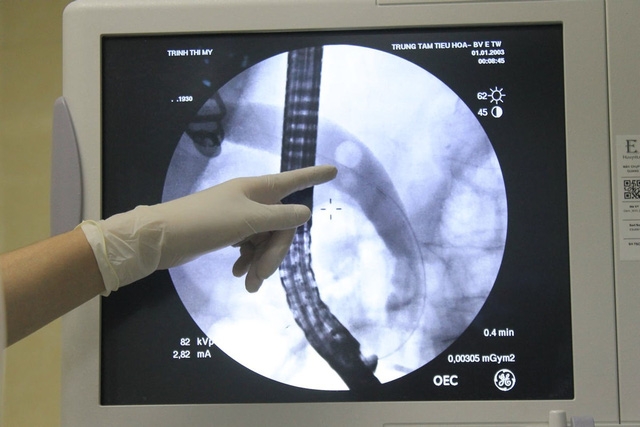

Ngày nay, với kỹ thuật can thiệp nội soi mật tụy ngược dòng, không ít người cao tuổi mắc sỏi ống mật chủ đã được can thiệp thành công. Điển hình như việc các bác sĩ Bệnh viện E (Hà Nội) vừa cứu sống bệnh nhân 91 tuổi bị nhiễm trùng đường mật nặng do sỏi OMC.

Bệnh nhân 91 tuổi, ở Kỳ Anh, Hà Tĩnh được ThS.BS Lê Văn Cơ, Khoa Nội tiêu hóa, Bệnh viện E T.Ư khám sàng lọc tuyến dưới phát hiện bị sỏi OMC cần phẫu thuật sớm. Trước đó, bệnh nhân có chỉ định phẫu thuật cắt túi mật nhưng vì tuổi cao lại mắc nhiều bệnh lý nền mạn tính như tăng huyết áp, đái tháo đường… nên nguy cơ biến chứng rất cao không thể mổ mở.Sau vài ngày bệnh nhân đã nhập viện trong tình trạng sốt, đau âm ỉ, liên tục vùng hạ sườn phải và thượng vị, tiểu sẩm màu, mệt mỏi, chán ăn… Kết quả thăm khám cho thấy bệnh nhân có tình trạng sốc nhiễm khuẩn đường mật, túi mật căng, giãn đường mật... do nhiễm trùng đường mật – theo dõi tắc mật do sỏi OMC.ThS.BS Nguyễn Ngọc Đại Lâm, Khoa Nội tiêu hóa, Bệnh viện E T.Ư cho biết, nếu mổ mở cổ điển có thể bệnh nhân sẽ không qua khỏi. Trong những trường hợp bệnh nhân tắc mật, nhiễm trùng đường mật nếu không được can thiệp kịp thời có thể dẫn tới tình trạng sốc nhiễm trùng nặng đe dọa đến tính mạng. Do đó, các bác sĩ quyết định nội soi mật tụy ngược dòng (ERCP) để lấy sỏi đường mật cho bệnh nhân.Viên sỏi nằm trong ống mật chủ có đường kính tương đối lớn khoảng 10mm gây nên giãn to ống mật chủ. Đây là trường hợp thứ 2 bệnh nhân cao tuổi được các bác sĩ Bệnh viện E T.Ư thực hiện kỹ thuật ERCP thành công trong năm qua. Trước đó, cũng có bệnh nhân nam, gần 100 tuổi được các bác sĩ Khoa Nội gan mật tiến hành ERCP lấy sỏi trong ống mật chủ.

Phương pháp lấy sỏi mật ngược dòng qua nội soi đường tiêu hoá trên - xâm lấn tối thiểu dần dần thay thế phương pháp phẫu thuật và thể hiện tính ưu việt như ít ảnh hưởng tới sức khỏe và thẩm mỹ, thời gian nằm viện ngắn, ít biến chứng, chi phí thấp. Bệnh nhân có thời gian phục hồi sức khỏe nhanh và bệnh nhân tránh được cuộc phẫu thuật lớn tiềm ẩn nhiều nguy cơ tai biến như chảy máu, nhiễm trùng vết mổ…, tiết kiệm chi phí nằm viện.Nhiễm trùng đường mật có thể dẫn đến nhiều biến chứng nghiêm trọng, đặc biệt xảy ra trên người bệnh lớn tuổi hoặc chậm trễ trong việc chẩn đoán và điều trị như: Áp xe gan, huyết khối tĩnh mạch cửa, viêm phúc mạc mật, hẹp đường mật, ung thư đường mật... Nhưng nguy hiểm nhất là nhiễm trùng huyết có thể dẫn đến suy thận cấp, sốc nhiễm trùng, tăng bilirubin máu… với tỷ lệ tử vong được báo cáo là 10% trong vòng 30 ngày.Do đó, các bác sĩ cảnh báo, người dân nên khám sức khỏe định kỳ hàng năm. Trường hợp đã phát hiện có sỏi đường mật thì nên tái khám mỗi sáu tháng và khi có biến chứng thì cần đến ngay các bệnh viện có thực hiện kỹ thuật nội soi mật tụy ngược dòng để can thiệp sớm. Ngoài ra, hiện nay trên thị trường vẫn quảng cáo nhiều loại thuốc có thể uống để làm tan sỏi túi mật, tuy nhiên, đây không phải là phương pháp điều trị phổ biến lại ẩn chứa nhiều nguy cơ khó lường, người dân cần cân nhắc thận trọng.